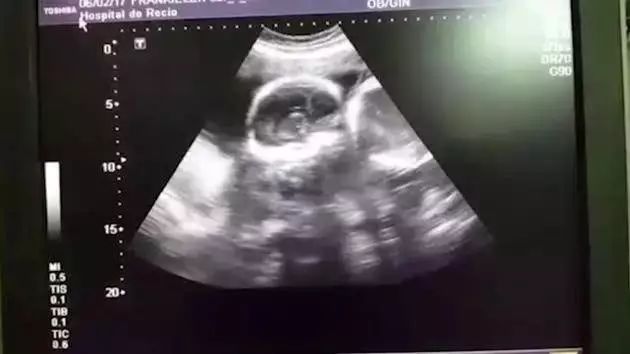

医生在看完B超后,

满脸笑容的说道:

“祝贺你们,

这是一对双胞胎!”

便对胚胎进行了超声检查,

原本应该超不过三天存活期的胎儿,

心脏居然还在跳动!